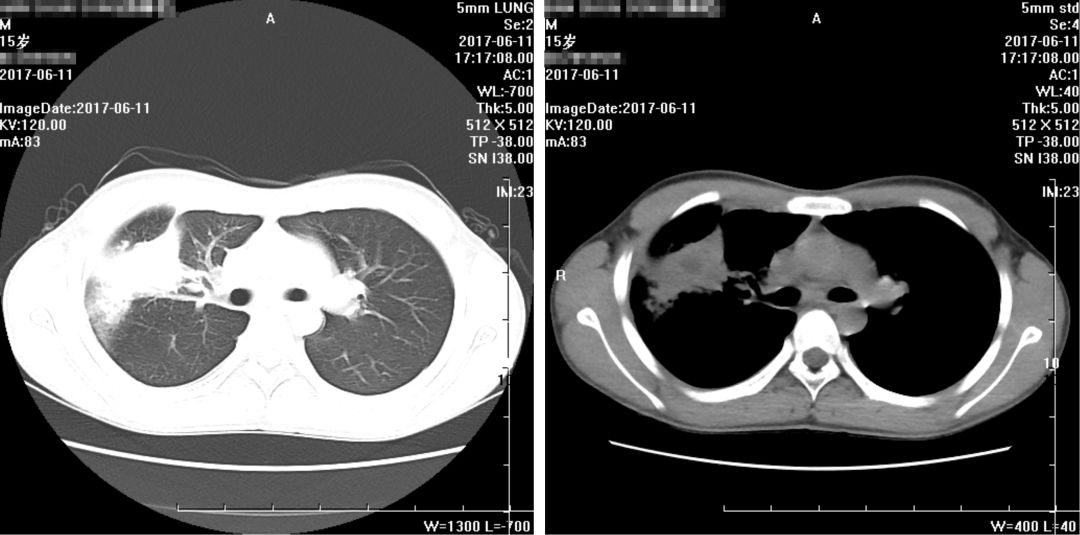

复查胸部CT报告:

1、右肺病变较前略有变化,部分减轻,尖段病变增多,请结合病原学检查;

2、右侧少许胸腔积液基本吸收;

3、纵隔及两侧腋窝多发淋巴结部分稍增大,较前未见明显变化。

余大致同前。

(2017年6月11日)

(2017年6月22日)

出院前一天,患者CT片结果如下:(2017年6月30日):